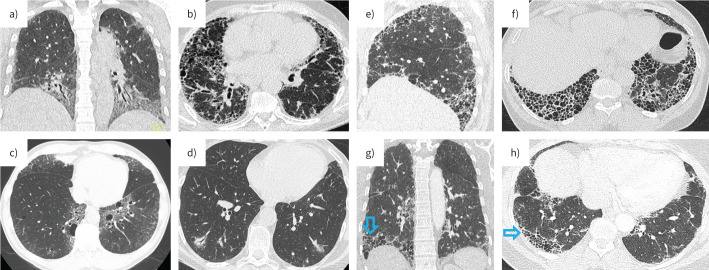

Connective tissue disease (CTD)-associated interstitial lung disease (ILD) is a complex condition arising in various autoimmune disorders, such as systemic sclerosis, Sjögren disease, systemic lupus erythematosus and idiopathic inflammatory myopathies. The broader term of systemic autoimmune rheumatic diseases (SARDs) and SARD-ILD are increasingly adopted in various guidelines to allow inclusion of other rheumatic diseases such as rheumatoid arthritis. SARD-ILD significantly impacts morbidity and mortality, with disease manifestations ranging from mild to severe and life-threatening. Epidemiological data show varying ILD prevalence rates amongst SARDs, with fibrosis being a key pathological component secondary to immune-mediated inflammation and tissue remodelling. SARD-ILD presents diverse histological patterns, primarily nonspecific interstitial pneumonia and usual interstitial pneumonia, each informing prognosis and guiding therapeutic strategies. Diagnosis relies on a comprehensive evaluation of clinical, serological, radiological and histological data, involving a multidisciplinary team. Immunosuppressive therapy is the cornerstone of treatment, with concurrent use of anti-fibrotic agents in specific progressive cases. Disease management is stratified by severity, with distinct guidelines for stable, progressive and rapidly progressive ILD. The prognosis varies across SARD-ILD types, influenced by specific markers, imaging features, and response to therapy. In severe cases, lung transplantation may be considered. Early recognition remains critical in optimising outcomes for SARD-ILD patients.